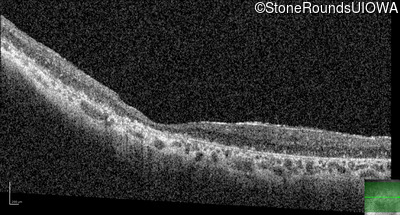

Age at visit: 41 years

This 41 year old man first came to medical attention at age 18 months when exotropia and amblyopia of his right eye were discovered. At age 11 vitreous strands and retinal vascular sheathing were seen. He has had poor night vision and constricted visual fields since his late teens. Later, at age 44 a traction retinal detachment was noted in his left eye and was treated with a scleral buckle.